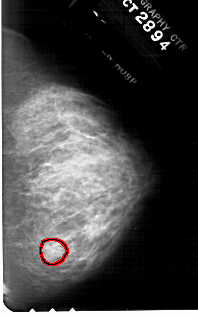

FILE: A_1781_1.RIGHT_CC.OVERLAY

TOTAL_ABNORMALITIES 1

ABNORMALITY 1

LESION_TYPE MASS SHAPE OVAL MARGINS ILL_DEFINED

ASSESSMENT 4

SUBTLETY 3

PATHOLOGY BENIGN

TOTAL_OUTLINES 1

BOUNDARY